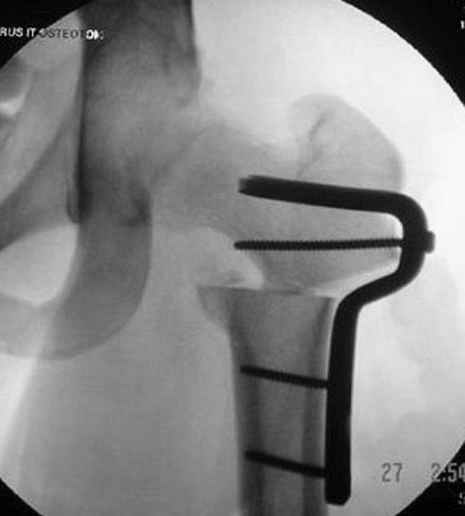

Если, например, доводится лечить больных с псевдартрозами шейки бедра, то надобность есть, и приходится. См. приложение.

На рисунке N1 предоперационный план лечения ложного сустава шейки бедра- линия ложного сустава, угол и направление введения импланта, клиновидная остеотомия в градусах и миллиметрах, второй снимок после коррекции, расчет, на сколько удлиняется конечность и размеры импланта;

N3 рисунок окончательный снимок, после операции моя рентгенограмма должен выглядеть примерно как эта картина. На N4 снимке клин перед удалением; N5 послеоперации 3 нед.; N6 окончательная рентгенограмма.